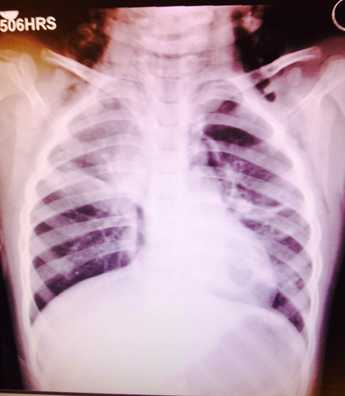

气胸

( pneumothorax )

气胸,还有什么问题,大家看出来没?